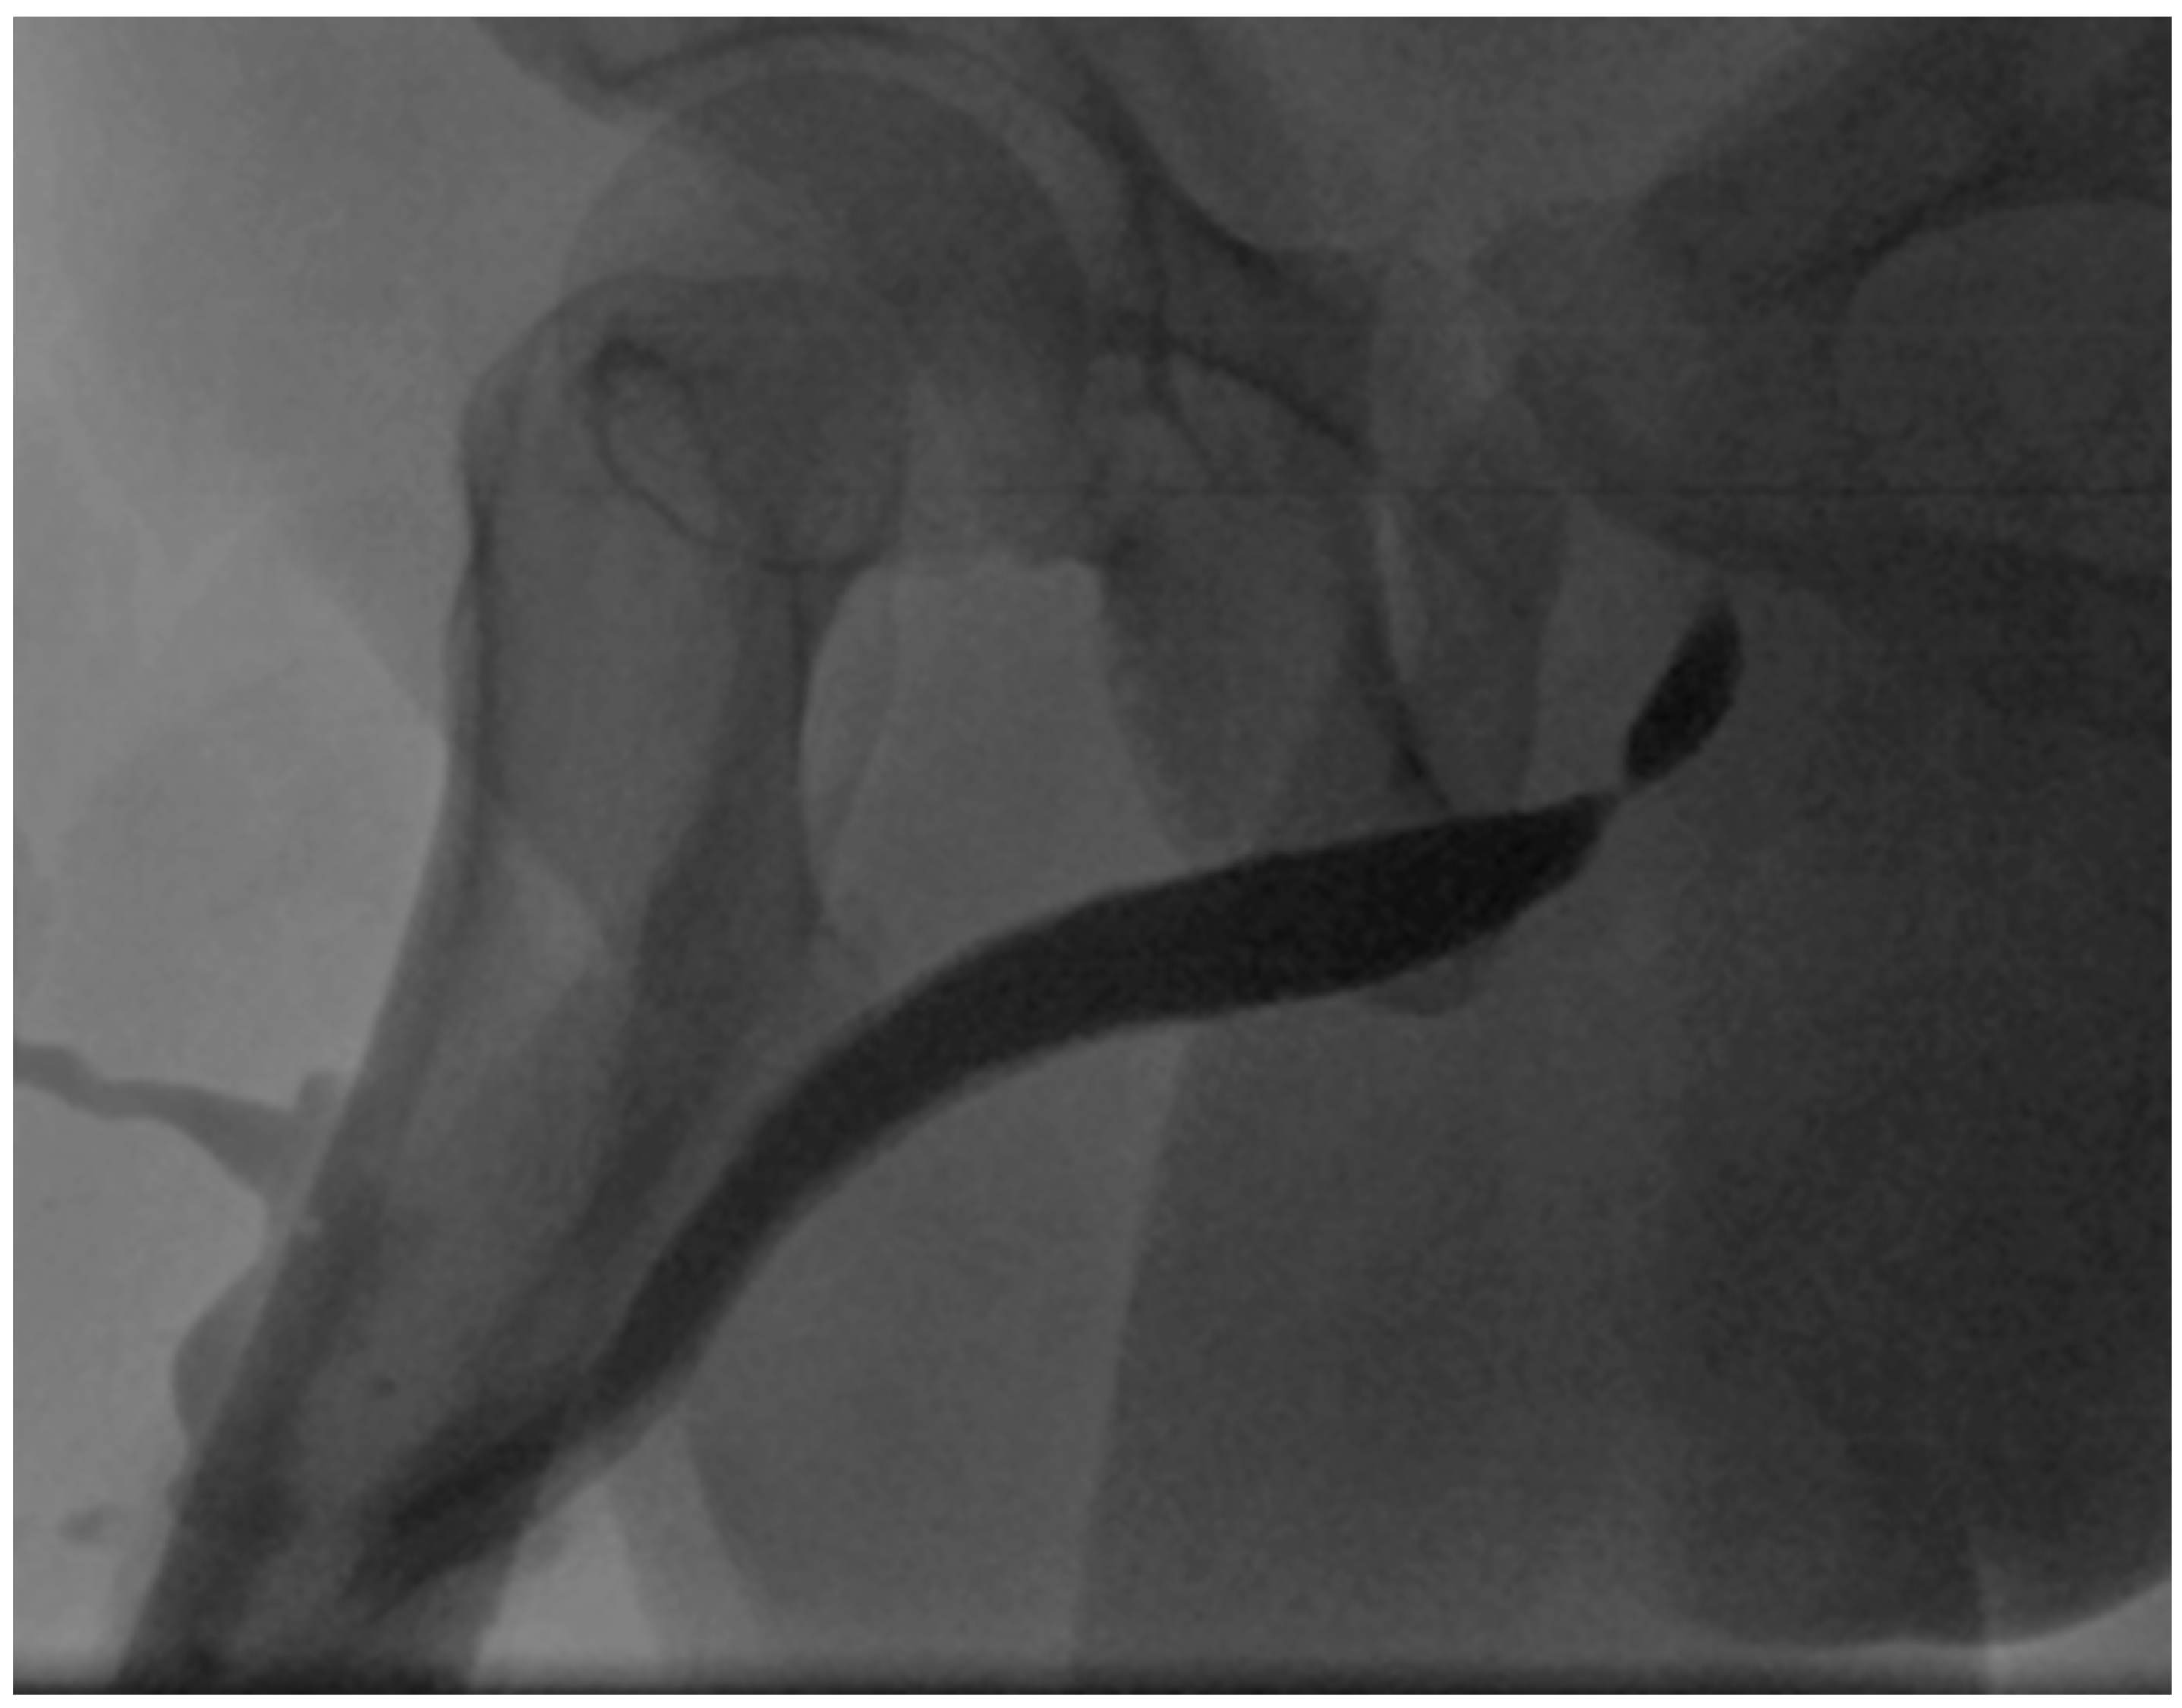

4. Case Report